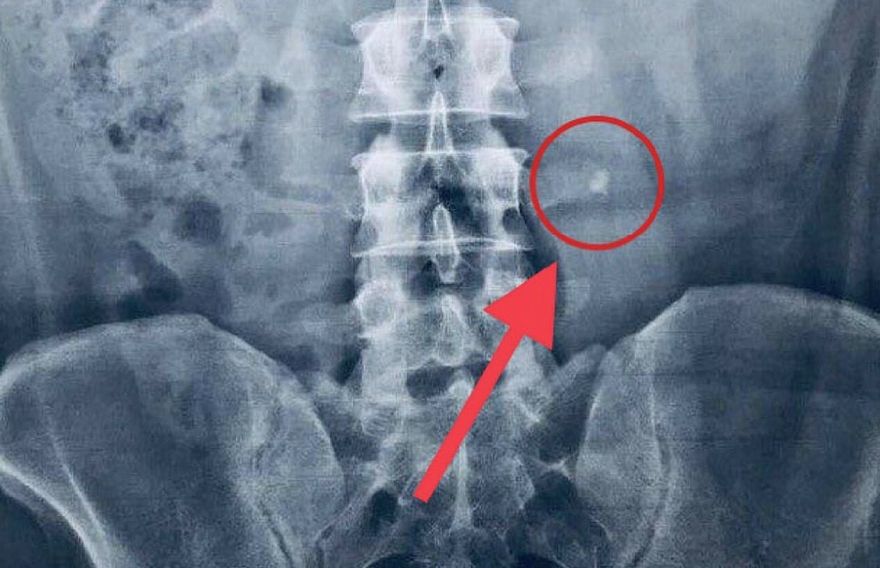

އަދީބަށް އެޑްމިޓްކޮށްގެން ފަރުވާ ދެމުން އަންނަނީ ކިޑްނީގައި އުފެދިފައިވާ ހިލަ ނައްތާލުމަށް ފަރުވާ ދެމުން އަންނާތީ އެވެ. ކިޑްނީގައި ހިލަ އުފެދުމުގެ އިތުރުން އޭނާގެ ހަށިގަނޑުގައި ސިސްޓުތަކެއް ވަނީ އުފެދިފަ އެވެ. އަދި ލޮލުގެ ފެނުމަށް އަސަރު ކުރާ ބައްޔެއް ކަމަށްވާ ގްލޫކޯމާ އަށް ވެސް އަދީބު ބޭސް ކުރެ އެވެ.

ޑޮކްޓަރުންނާ ހަވާލާދީ އަދީބުގެ އާއިލާއިން ބުނެފައި ވަނީ ބޭސް ބޭނުންކޮށްގެން ހިލަކޮޅު ނައްތާ ނުލެވިއްޖެ ނަމަ ލޭޒާ ބޭނުންކޮށްގެން އެކަން ކުރަންޖެހިދާނެ ކަމަށެވެ. ކިޑްނީގައި އުފެދުނު ހިލަކޮޅުބޭހުގެ ސަބަބުން މިހާރު އިނީ ޔުރެތްރާ ނުވަތަ ހީސް ހޮޅި ކައިރީގަ އެވެ. އަދީބުގެ ހާލު އަދިވެސް ރަނގަޅު ނޫން ކަމަށް އާއިލާއިން ބުނެ އެވެ.

"އަދީބުގެ ކިޑްނީ އާއި ބްލެޑާ [ޔުރެތުރާ] އާ ދެމެދަށް ވެއްޓިފައިވާ ހިލަކޮޅު އަދިވެސް ޑޮކްޓަރުންނަށް ފަރުވާދީގެން ފްލަޝް ކުރެވިފައެއް ނުވޭ. މިކަމުގެ ސަބަބުން އަދީބުގެ ވާތް ފަރާތުގެ ކިޑްނީ ވަނީ ދުޅަވެފައި،" ނަޝްވާ ވިދާޅުވި އެވެ.